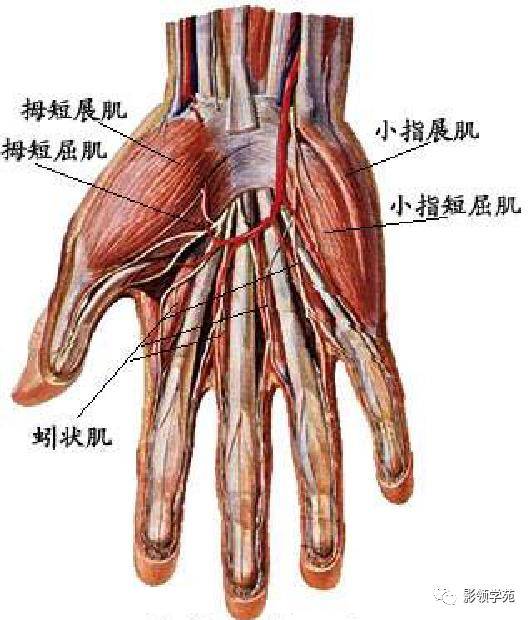

手掌动脉走向

手掌动脉走向